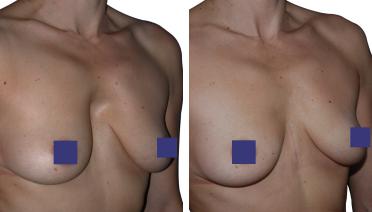

Petto Escavato: risultati prima e dopo

In questa pagina, troverà i risultati di questa operazione a seconda del tipo di Pectus : mediale, asimmetrico, più o meno profondo o lungo.

Tipo 3 : Asimmetrico,